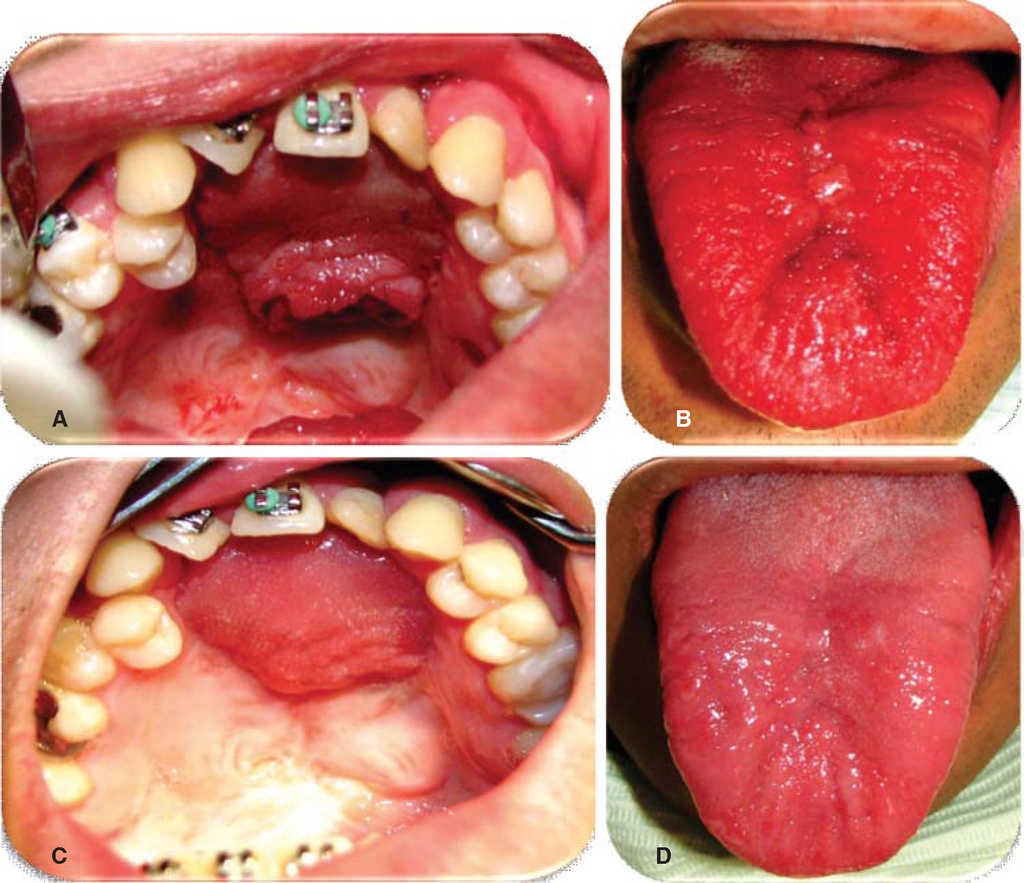

Evolución. Se realizan controles semanales a los 7, 14, 21 y 28 días observándose en los controles de el día 7, 14 y 21 excelente evolución, se observa mucosas bien hidratadas con buena coloración, herida quirúrgica sin datos de dehiscencia, infección o compromiso de vascularidad (Figuras 5 y 6). Se observa buena movilidad de lengua y sin alteraciones en la fonación. En el día 21 se realiza pinzamiento y separación de colgajo de lengua bajo anestesia local sin complicaciones o accidentes, se cita en una semana y se medica con amoxicilina VO 500 mg cada ocho horas por siete días e ibuprofeno VO 400 mg cada ocho horas por cinco días. En el control del día 28 se observan heridas quirúrgicas limpias sin datos de infección o dehiscencia, fístula oronasal cerrada al 100%, dorso de la lengua sin alteraciones funcionales o estéticas. Se da de alta al paciente y se cita en un mes para control.

Figura 6 Pinzamiento y retiro de colgajo lingual. A. Lecho quirúrgico retiro de colgajo lingual. B. Lecho quirúrgico sitio donante. C. Cierre 100% fístula palatina. D. Sutura de sitio donante.